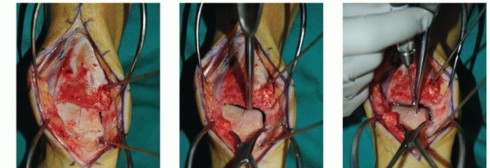

- TECH FIG 2 • A,B. Identifying the extent of the talar shoulder lesion. (continued)

Define the extent of the OLT (TECH FIG 2A,B).

- TECH FIG 2 • (continued) C-E. Excision of the talar shoulder lesion using the microsagittal and oscillating saws. F. Talar shoulder lesion removed.

Excise the diseased portion of the talus (TECH FIG 2C-F).

Reciprocating and microsagittal saw (use cool saline to limit risk of heat necrosis) May need a small curette and rasp as well